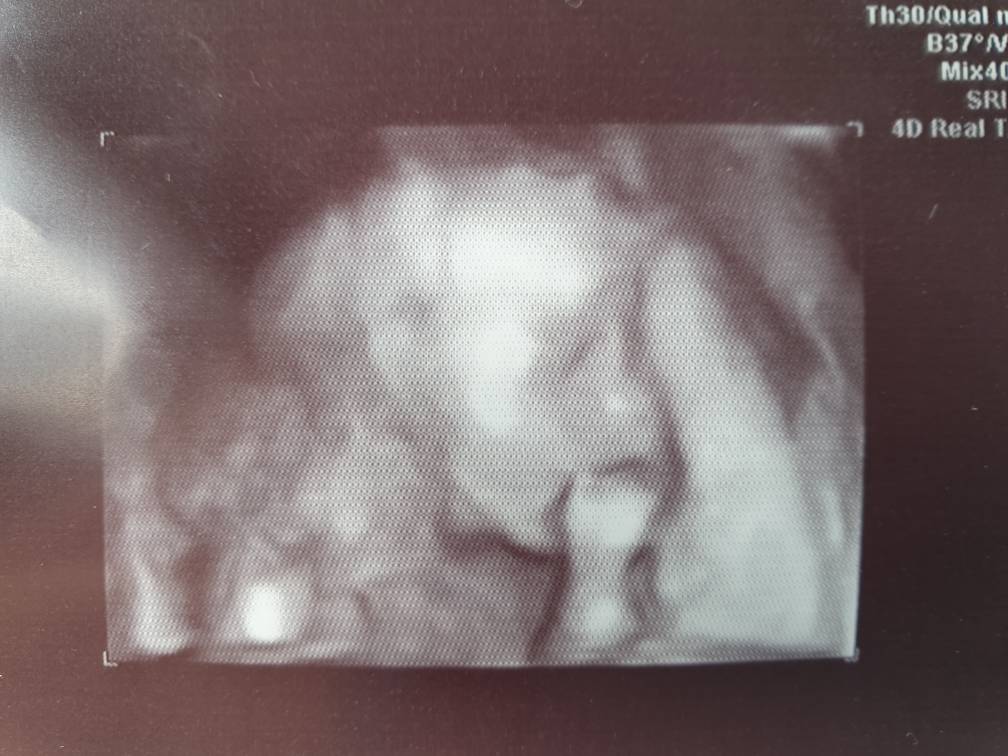

Witam sie dzis po połówkowych! U nas 23 t z OM a z USG 24

maluch ma 611 gramow i jest zdrowy!

Zobacz załącznik 1017437